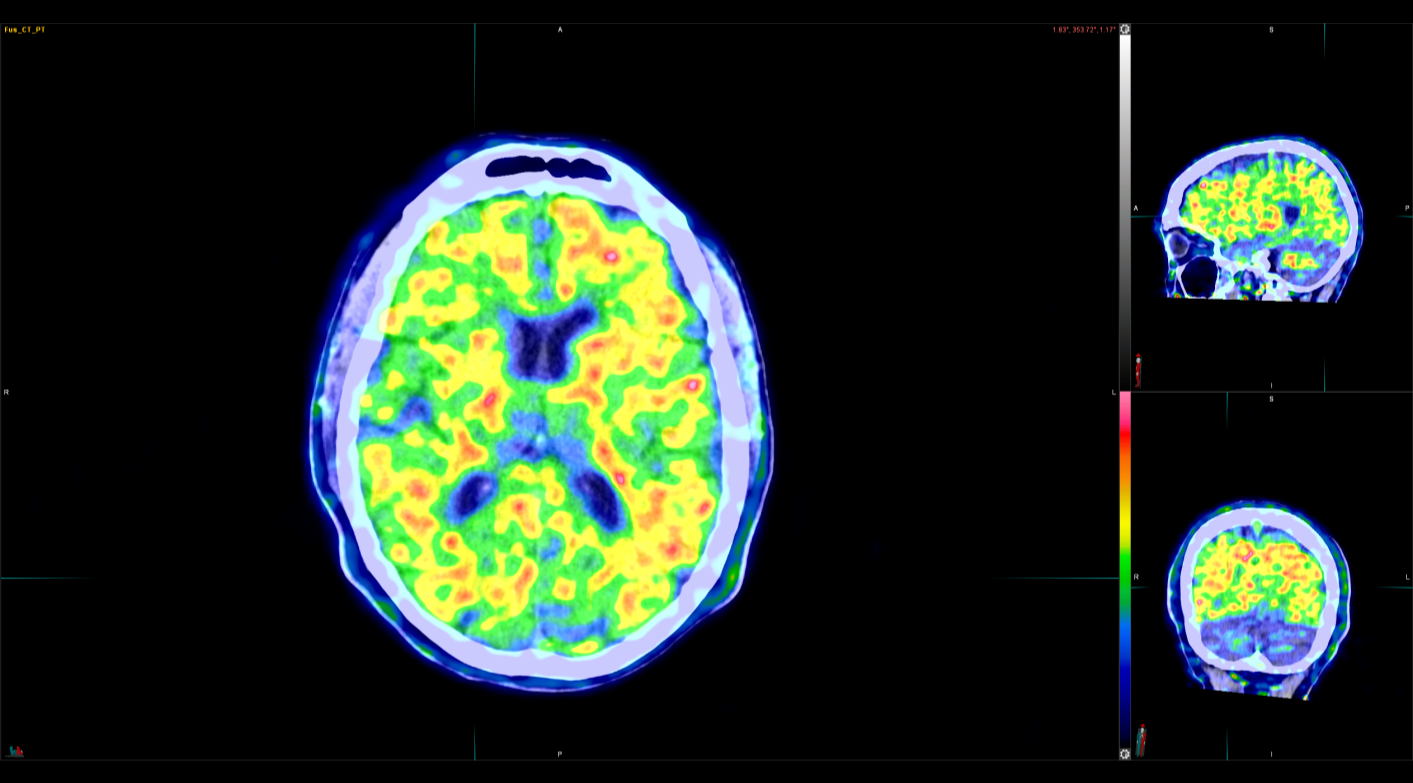

PET CT Με μέγιστη ακρίβεια ελάχιστη επιβάρυνση Το Τμήμα PET/CT Από τον Δεκέμβριο του 2025, το Τμήμα PET/CT του ΥΓΕΙΑ εξοπλίστηκε με τον υπερσύγχρονο τομογράφο Biograph Trinion PET/CT. Πρόκειται για το πέμπτο μηχάνημα με το οποίο αναβαθμίζεται το τμήμα από την αρχή λειτουργίας του το 2004. Το Trinion είναι το πιο πρόσφατης κατασκευής διαθέσιμο ψηφιακό PET CT παγκοσμίως. Ο τομογράφος διαθέτει ανιχνευτές LSO, CT 64 τομών και το πολυδύναμο λογισμικό SYNGO. Η τεχνολογία αυτή προσφέρει εξαιρετική απεικόνιση των βιολογικών διεργασιών σε μοριακό επίπεδο, αναδεικνύοντας τόσο τους υγιείς όσο και τους παθολογικούς ιστούς. Biograph Trinion AI-Powered PET/CT: Η νέα γενιά ακρίβειας. Το PET/CT που βλέπει βαθύτερα, καθαρότερα, ταχύτερα. Χαμηλότερη δόση – Ίδια ή καλύτερη ποιότητα

Κρύσταλλοι με βάση Lutetium για ακριβή απεικόνιση

Πραγματικό ultra fast Time-of-flight για βελτιστοποίηση του SNR και επίτευξη γρηγορότερων σαρώσεων, με λιγότερη εγχυμένη δόση και καλύτερη ποιότητα εικόνας. Με την πραγματική τεχνολογία ultra fast Time–of–flight (239ps) υπολογίζουμε με μεγαλύτερη ακρίβεια το σημείο στο οποίο πραγματοποιήθηκε η εξαύλωση, και να βελτιώνουμε τον λόγο σήματος/θόρυβο(SNR). Αυτό έχει ως αποτέλεσμα να απορρίπτονται οι ψευδείς κρούσεις, επιτυγχάνοντας μεγαλύτερη ευαισθησία, καλύτερη ποιότητα εικόνας και μικρότερο χρόνο εξέτασης. FlowMotion™ Al – Εξατομίκευση των σαρώσεων μέσω ειδικού αλγορίθμου τεχνητής νοημοσύνης.

Σε μία φράση: Το Biograph Trinion δεν είναι απλώς η νεότερη πλατφόρμα digital PET/CT. Αποτελεί την μετάβαση από την καταγραφή, στην πραγματική κατανόηση της νόσου και κατ’ έκταση στην ακριβέστερη θεραπεία της.